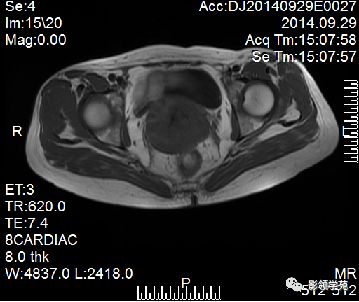

宫颈癌可表现为类圆形或不规则形肿块,在T2WI上表现为均匀或欠均匀的高信号,与正常宫颈基质及宫旁脂肪形成良好的自然对比。

- Ⅰ期肿瘤:侵犯宫颈基质,T2WI等信号肿块,宫颈管扩大及宫颈纤维基质中断

- Ⅱ期肿瘤:宫颈增大,宫旁肿块或宫旁脂肪组织内出现异常信号的粗线状影

- Ⅲ期肿瘤:侵犯至阴道下部,外延至盆壁,或出现肾积水。

- Ⅳ期肿瘤:膀胱壁或直肠壁低信号中断,膀胱壁或直肠壁增厚或腔内肿块。